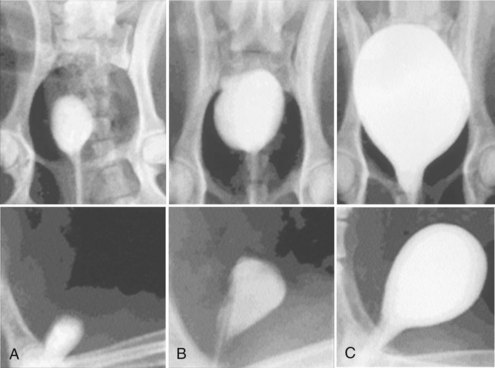

A system for the progressive expansion of native bladder tissue has also been used for augmenting bladder volumes (Satar et al, 1999). Beagle dog bladders were divided horizontally into two segments: a superior bladder neoreservoir, and an intact smaller bladder inferiorly with both ureters left intact and draining. A Silastic catheter was threaded into the newly formed, superiorly located neoreservoir and connected to an injection port, which was secured subcutaneously. Four weeks after surgery, a saline-antibiotic solution was injected daily into the palpable injection port, dilating the neoreservoir through the Silastic catheter. Within 30 days after progressive dilation, the neoreservoir volume was expanded at least 10-fold (Fig. 19–8). Urodynamic studies showed normal compliance in all animals, and microscopic examination of the expanded neoreservoir tissue showed a normal histology. A series of immunocytochemical studies demonstrated that the dilated bladder tissue maintained normal phenotypic characteristics (Satar et al, 1999).

Figure 19–8 Progressive bladder dilation can be performed with adequate increases in capacity. Cystography of bladder neoreservoir before progressive dilation (A) is compared with cystography results after progressive dilation (B) and with cystogram showing dilated neoreservoir and intact bladder segment (C).

Cystectomy-only and nonseeded controls maintained average capacities of 22% and 46% of preoperative values, respectively. An average bladder capacity of 95% of the original precystectomy volume was achieved in the cell-seeded tissue engineered bladder replacements. These findings were confirmed radiographically (Fig. 19–10). The subtotal cystectomy reservoirs that were not reconstructed and the polymer-only reconstructed bladders showed a marked decrease in bladder compliance (10% and 42% total compliance). The compliance of the cell-seeded tissue-engineered bladders showed almost no difference from preoperative values that were measured when the native bladder was present (106%). Histologically, the nonseeded scaffold bladders presented a pattern of normal urothelial cells with a thickened fibrotic submucosa and a thin layer of muscle fibers. The retrieved tissue-engineered bladders showed a normal cellular organization, consisting of a trilayer of urothelium, submucosa, and muscle (Fig. 19–11). Immunocytochemical analyses confirmed the muscle and urothelial phenotype. S-100 staining indicated the presence of neural structures (Oberpenning et al, 1999). These studies, performed with polyglycolic acid–based scaffolds, have been repeated by other investigators, showing similar results in large numbers of animals long-term (Jayo et al, 2008a, 2008b). The strategy of using biodegradable scaffolds with cells can be pursued without concerns for local or systemic toxicity (Kwon et al, 2008). However, not all scaffolds perform well if a large portion of the bladder needs replacement. In a study using SIS for subtotal bladder replacement in dogs, both the unseeded and cell-seeded experimental groups showed graft shrinkage and poor results (Zhang et al, 2006b). The type of scaffold used is critical for the success of these technologies. The use of bioreactors, wherein mechanical stimulation is started at the time of organ production, has also been proposed as an important parameter for success (Farhat et al, 2008).

Figure 19–10 Radiographic cystograms in beagles 11 months after subtotal cystectomy without reconstruction (A); with reconstruction using a polymer without cells (B); and with reconstruction with a polymer and cell-seeded tissue-engineered organ (C). Organs after trigone-sparing cystectomy retained a small-sized reservoir. Tissue-engineered neobladders showed a normal configuration and a larger capacity than the trigones grafted with polymer only.